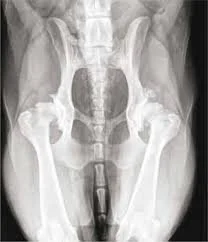

Arthritis is one of the most common reasons older dogs slow down. Many senior dogs with arthritis do not cry out or show dramatic lameness at first. Instead, owners may notice stiffness after rest, slower rising, trouble with stairs, limping, or less interest in walks and play. Dr. Roger Hart at Bushnell Animal Clinic explains the signs of arthritis in older dogs, available treatment options, and when a dog should be evaluated.